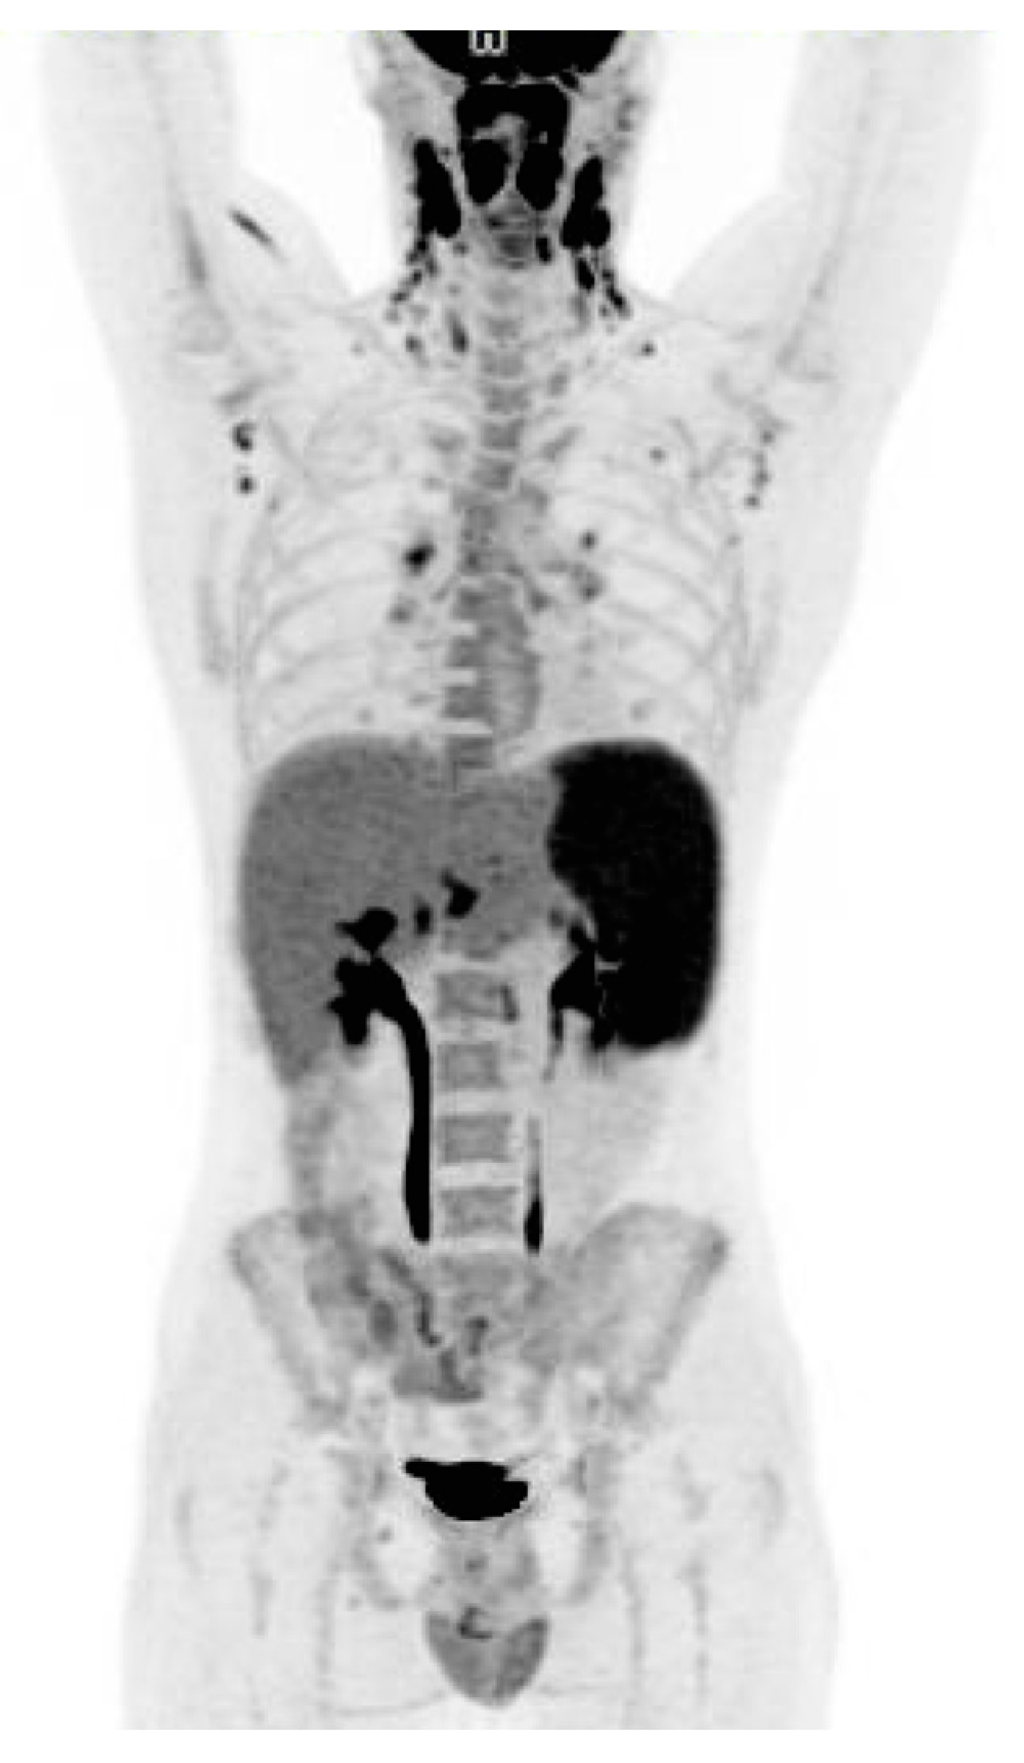

Figure 1. A 21-year-old man presented with 6 weeks of unexplained fever, pharyngitis, enlarged cervical neck lymph nodes, night sweats and severe fatigue. The patient was treated as an outpatient with antibiotics for acute tonsillitis twice without any improvement. He had persistent daily fever and a 6 kg unintentional weight loss. No significant past medical history. Epstein-Barr virus (EBV) and Cytomegalovirus (CMV) titers drawn one week after debut of symptoms were negative. Three months before presenting with symptoms the patient had been travelling in South East Asia for 3.5 months. He had not been sick during his travel abroad. Physical examination was significant for lymphadenopathy at the cervical neck. No splenomegaly was noted. At admission white blood cells was 13.0 × 109/L (normal range: 3.5–8.8 × 109/L) with 10.0 × 109/L lymphocytes (normal range: 1.0–3.5 × 109/L). Alanine aminotransferase (ALT) was elevated at 104 U/L (normal range: 10–70 U/L) and Lactate dehydrogenase (LDH) was elevated at 939 U/L (normal range: 105–205 U/L). Due to concern of malignant lymphoma an 18F-FDG PET/CT was performed (Figure 1). The scan revealed pathologically 18F-FDG uptake in enlarged lymph nodes in the bilateral regions of neck, axillas, lung hili, and in an enlarged spleen (18 cm). Findings were suspicious for malignant lymphoma. A lymph node biopsy was considered.